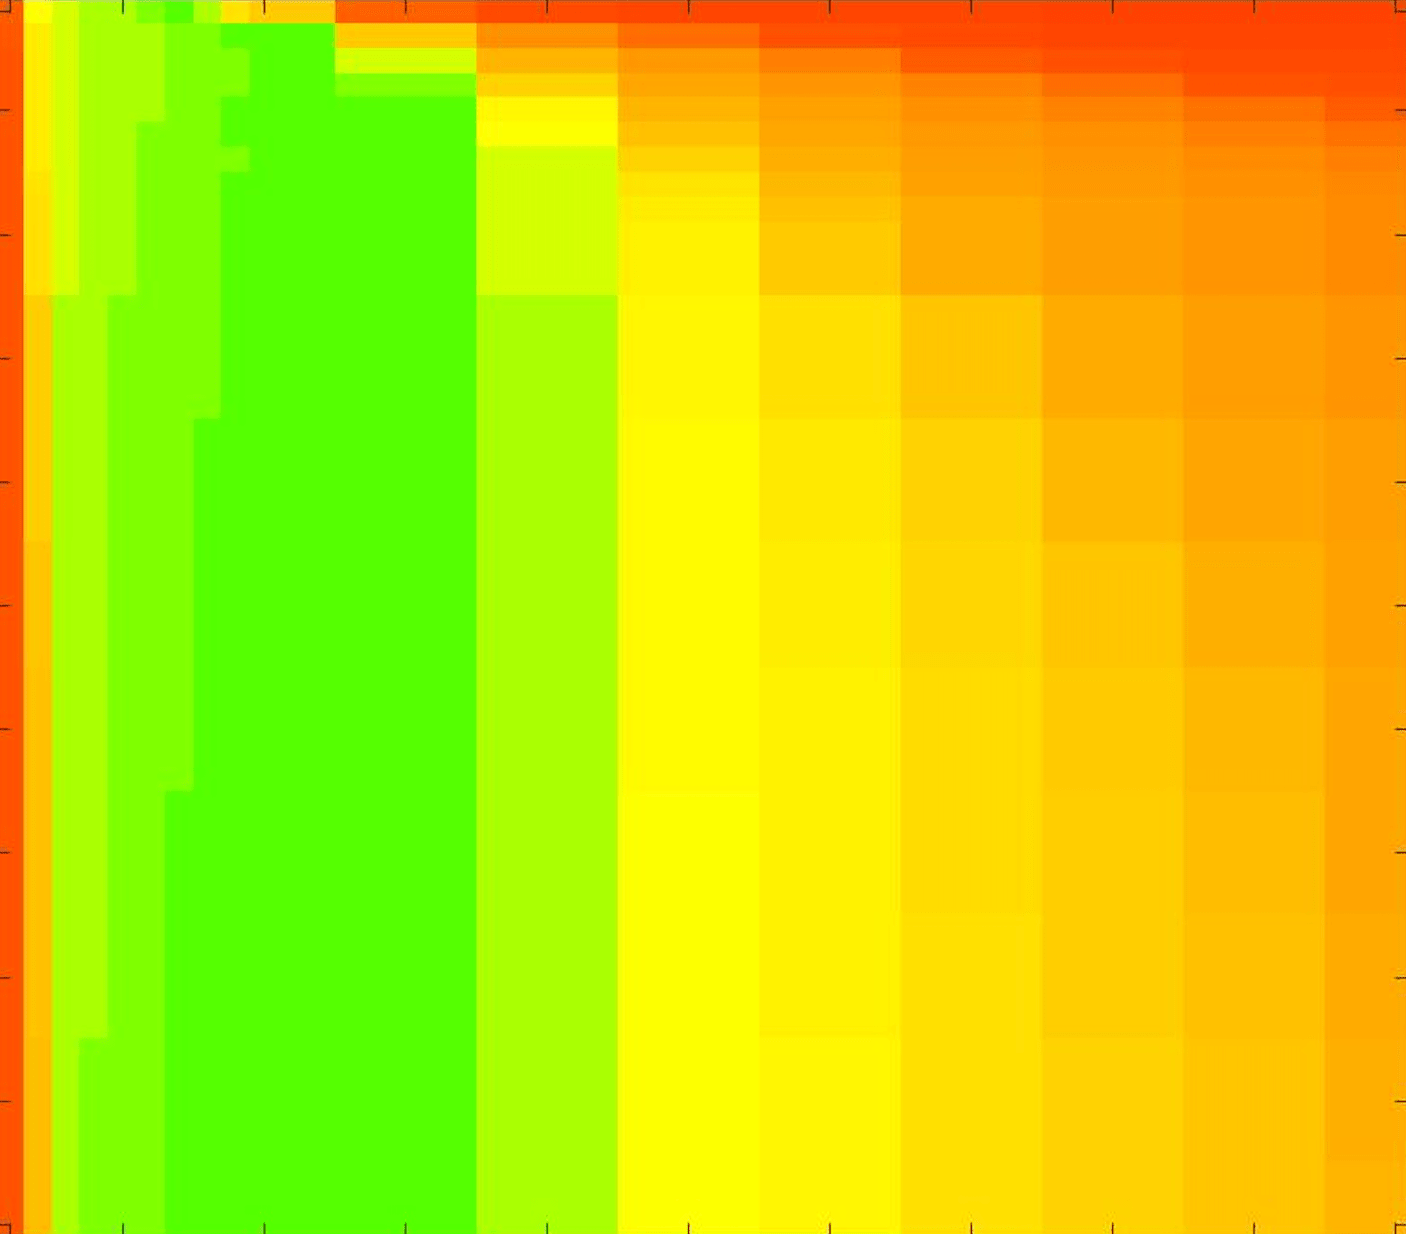

where refers to the number of points in the enclosed region. This takes values in the range , with higher TC values indicating a more accurate segmentation. In the following we will represent accuracy visually from red () to green (), with the intermediate scaling of colours used shown in Fig. 8. This will be particularly relevant in §7.2.

The TC values for the parameter sets are presented as heatmaps in Figs. 11–13. A heatmap is a convenient way to display accuracy results for hundreds of tests concisely. In Fig. 9 we give an example heatmap with the same axes used for those in Figs. 11–13. For each of the combinations of parameter values we give the TC value of the segmentation result and represent it by the appropriate colour. The corresponding colour scale is shown in Fig. 8. Qualitatively, the more green areas of the heatmap the more accurate the model is for a wider set of parameters. Example results for Test Image 5 when varying (with ) for the proposed model are given in Fig. 10. Here it can be seen what each accuracy result corresponds to visually.

Note. The axes have been removed from the heatmaps in Figs. 11–13 for presentational clarity. However, to be explicit, the axes used in all heatmaps are the same as those in Fig. 9.

Synthetic Images. These results are presented in Fig. 11. For Test Images 1–2 we see poor parameter robustness from all competing models, except for GAV which performs reasonably well. However, the proposed model has minimal parameter sensitivity for these images, with good results achieved for almost every combination of values tested. For Test Image 3 all models have a reasonable parameter range (except for RSF), however the proposed model gives better quality results for a wider parameter range. The other models achieve reasonable results here as the foreground intensity of the ground truth is greater than the background , whereas for Test Images 1–2 they are equal . These results highlight the key advantage of the proposed model.

Real Images. In Fig 12 we present results for Test Images 4–6. Here, the proposed model performs in a similar way to its competitors because these images are more typical selective segmentation problems in the sense that there is a clear distinction between the foreground and background intensities. In particular, the values in each case are: Test Image 4 , Test Image 5 , and Test Image 6 . It can be seen that the proposed model is competitive compared to previous approaches. The performance is quite poor for Test Image 5, but is arguably still the best for this challenging case. In Fig. 13 we present results for Test Images 7–9. Here the proposed model outperforms previous approaches significantly for each image. This is mainly due to the type of image considered. Specifically, the true intensities are: Test Image 7 , Test Image 8 , and Test Image 9 . The proposed model is capable of achieving results where , with other models failing completely in these cases.